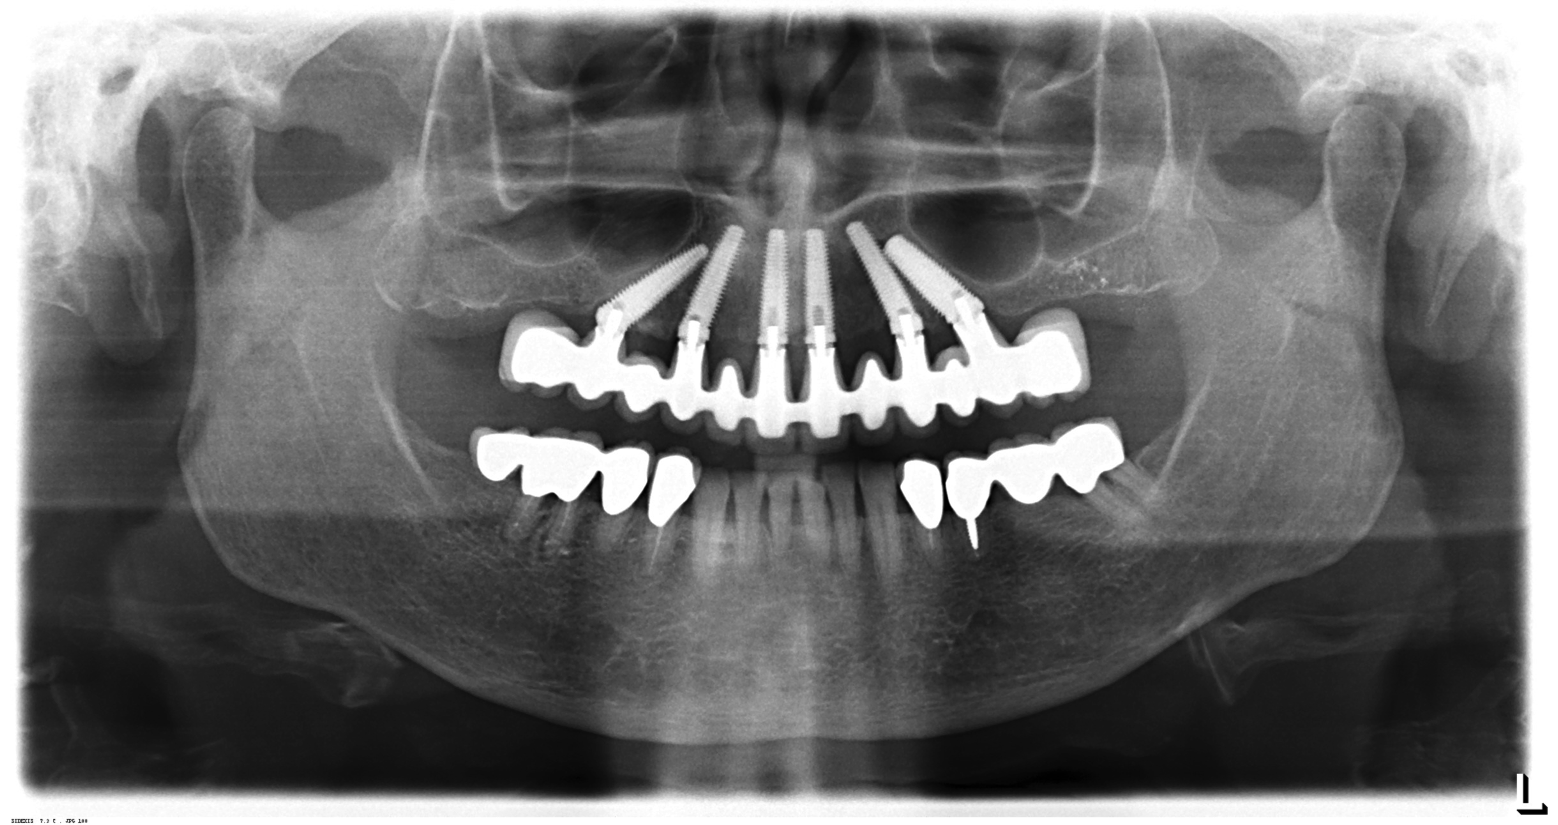

With the increased application of this concept, more options have been introduced, including 24-degree and 36-degree correction (Figure 11 through Figure 13). At present, larger angular corrections are available with external hexagon connection systems, while the 12-degree connection is also available in most internal connection configurations.

Fig 11. Panorex of clinical application of dual-axis principles. From left to right: 36-degree tooth No. 4; 24-degree tooth No. 6; 12-degree tooth No. 8; 12-degree tooth No. 9; 24-degree tooth No. 11; and 36-degree tooth No. 13. Angulation is designed to avoid maxillary sinus and buccal constraints of the anterior maxilla. (Image courtesy of Costa Nicolopoulos, BDS, Dubai, United Arab Emirates)

Figure 11